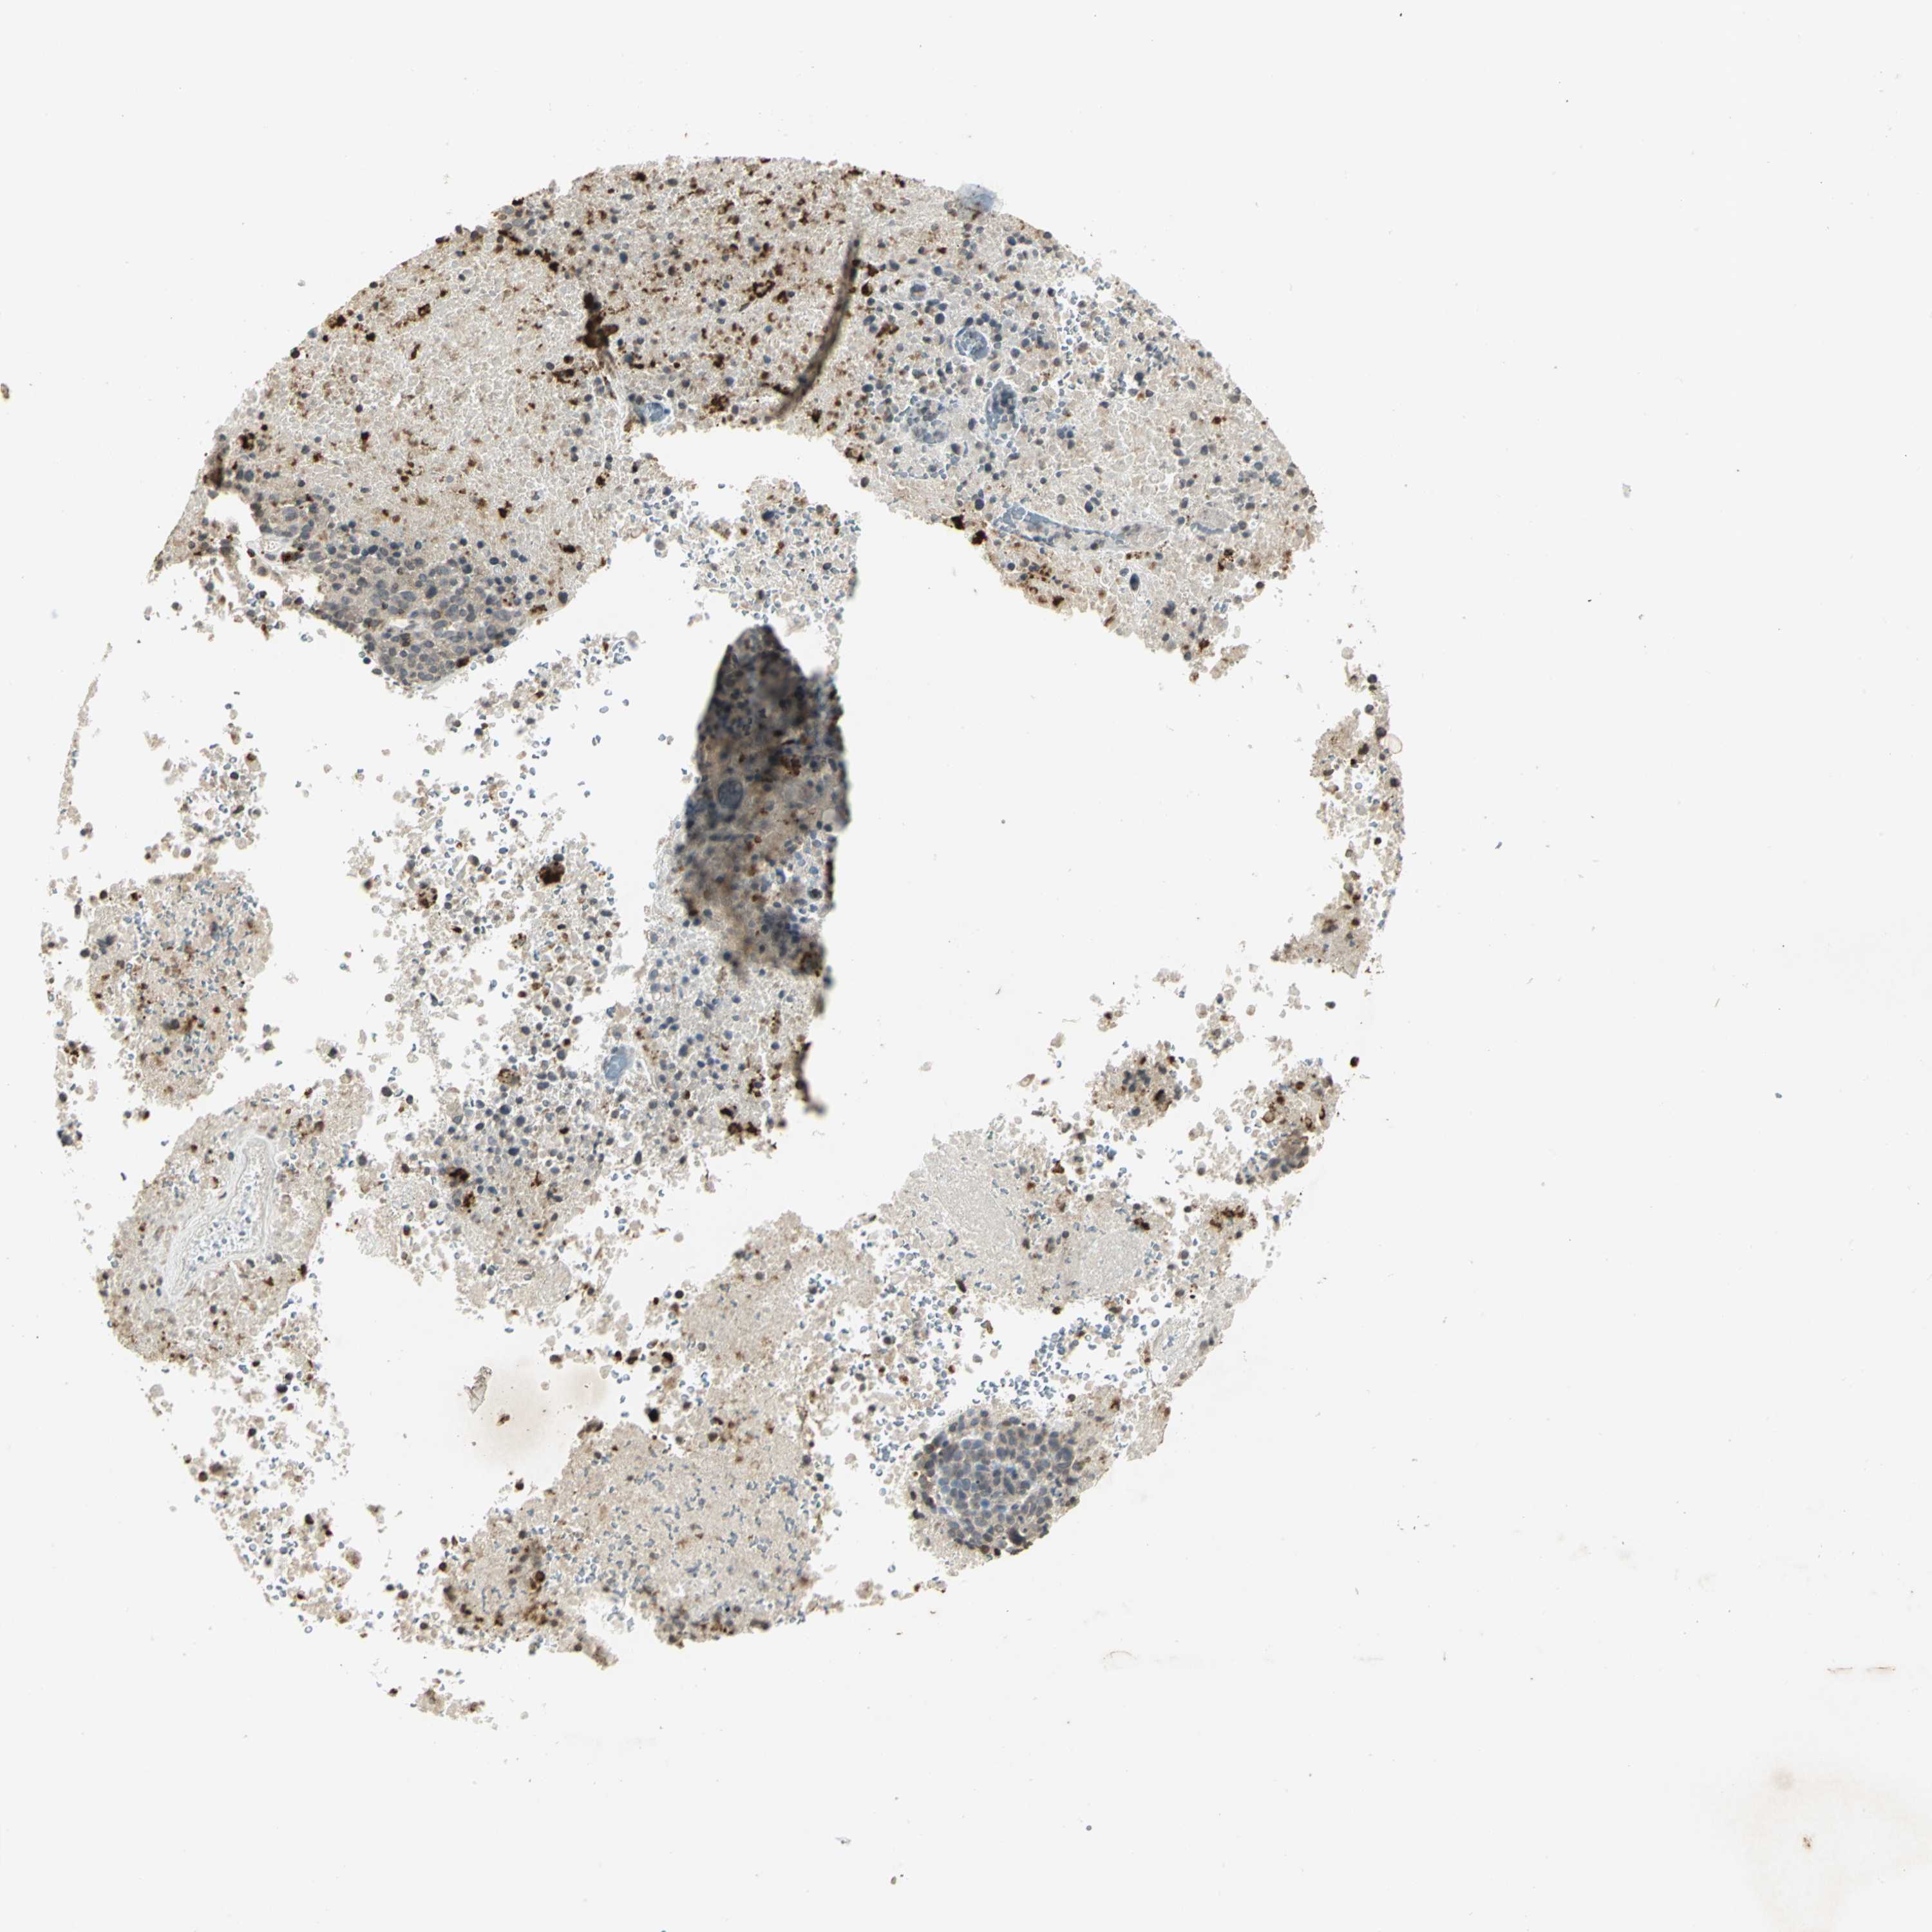

MELANOMA - Protein expressioni

A mouse-over function shows sample information and annotation data. Click on an image to view it in a full screen mode. Samples can be filtered based on level of antibody staining by selecting one or several of the following categories: high, medium, low and not detected. The assay and annotation is described here.

Note that samples used for immunohistochemistry by the Human Protein Atlas do not correspond to samples in the TCGA dataset.

Antibody stainingi

Antibody staining in the annotated cell types in the current human tissue is reported as not detected, low, medium, or high, based on conventional immunohistochemistry profiling in selected tissues. This score is based on the combination of the staining intensity and fraction of stained cells.

Each image is clickable and will lead to virtual microscopy that enables deeper exploration of all samples and also displays staining intensity scores, fraction scores and subcellular localization as well as patient and tissue information for each sample.

Antibody HPA018467

Antibody CAB005247

Staining

High

Medium

Low

Not detected

Intensity

Strong

Moderate

Weak

Negative

Quantity

>75%

75%-25%

<25%

None

Location

Nuclear

Cytoplasmic/membranous

Cytoplasmic/membranous,nuclear

Malignant melanoma, NOS

Malignant melanoma, Metastatic site